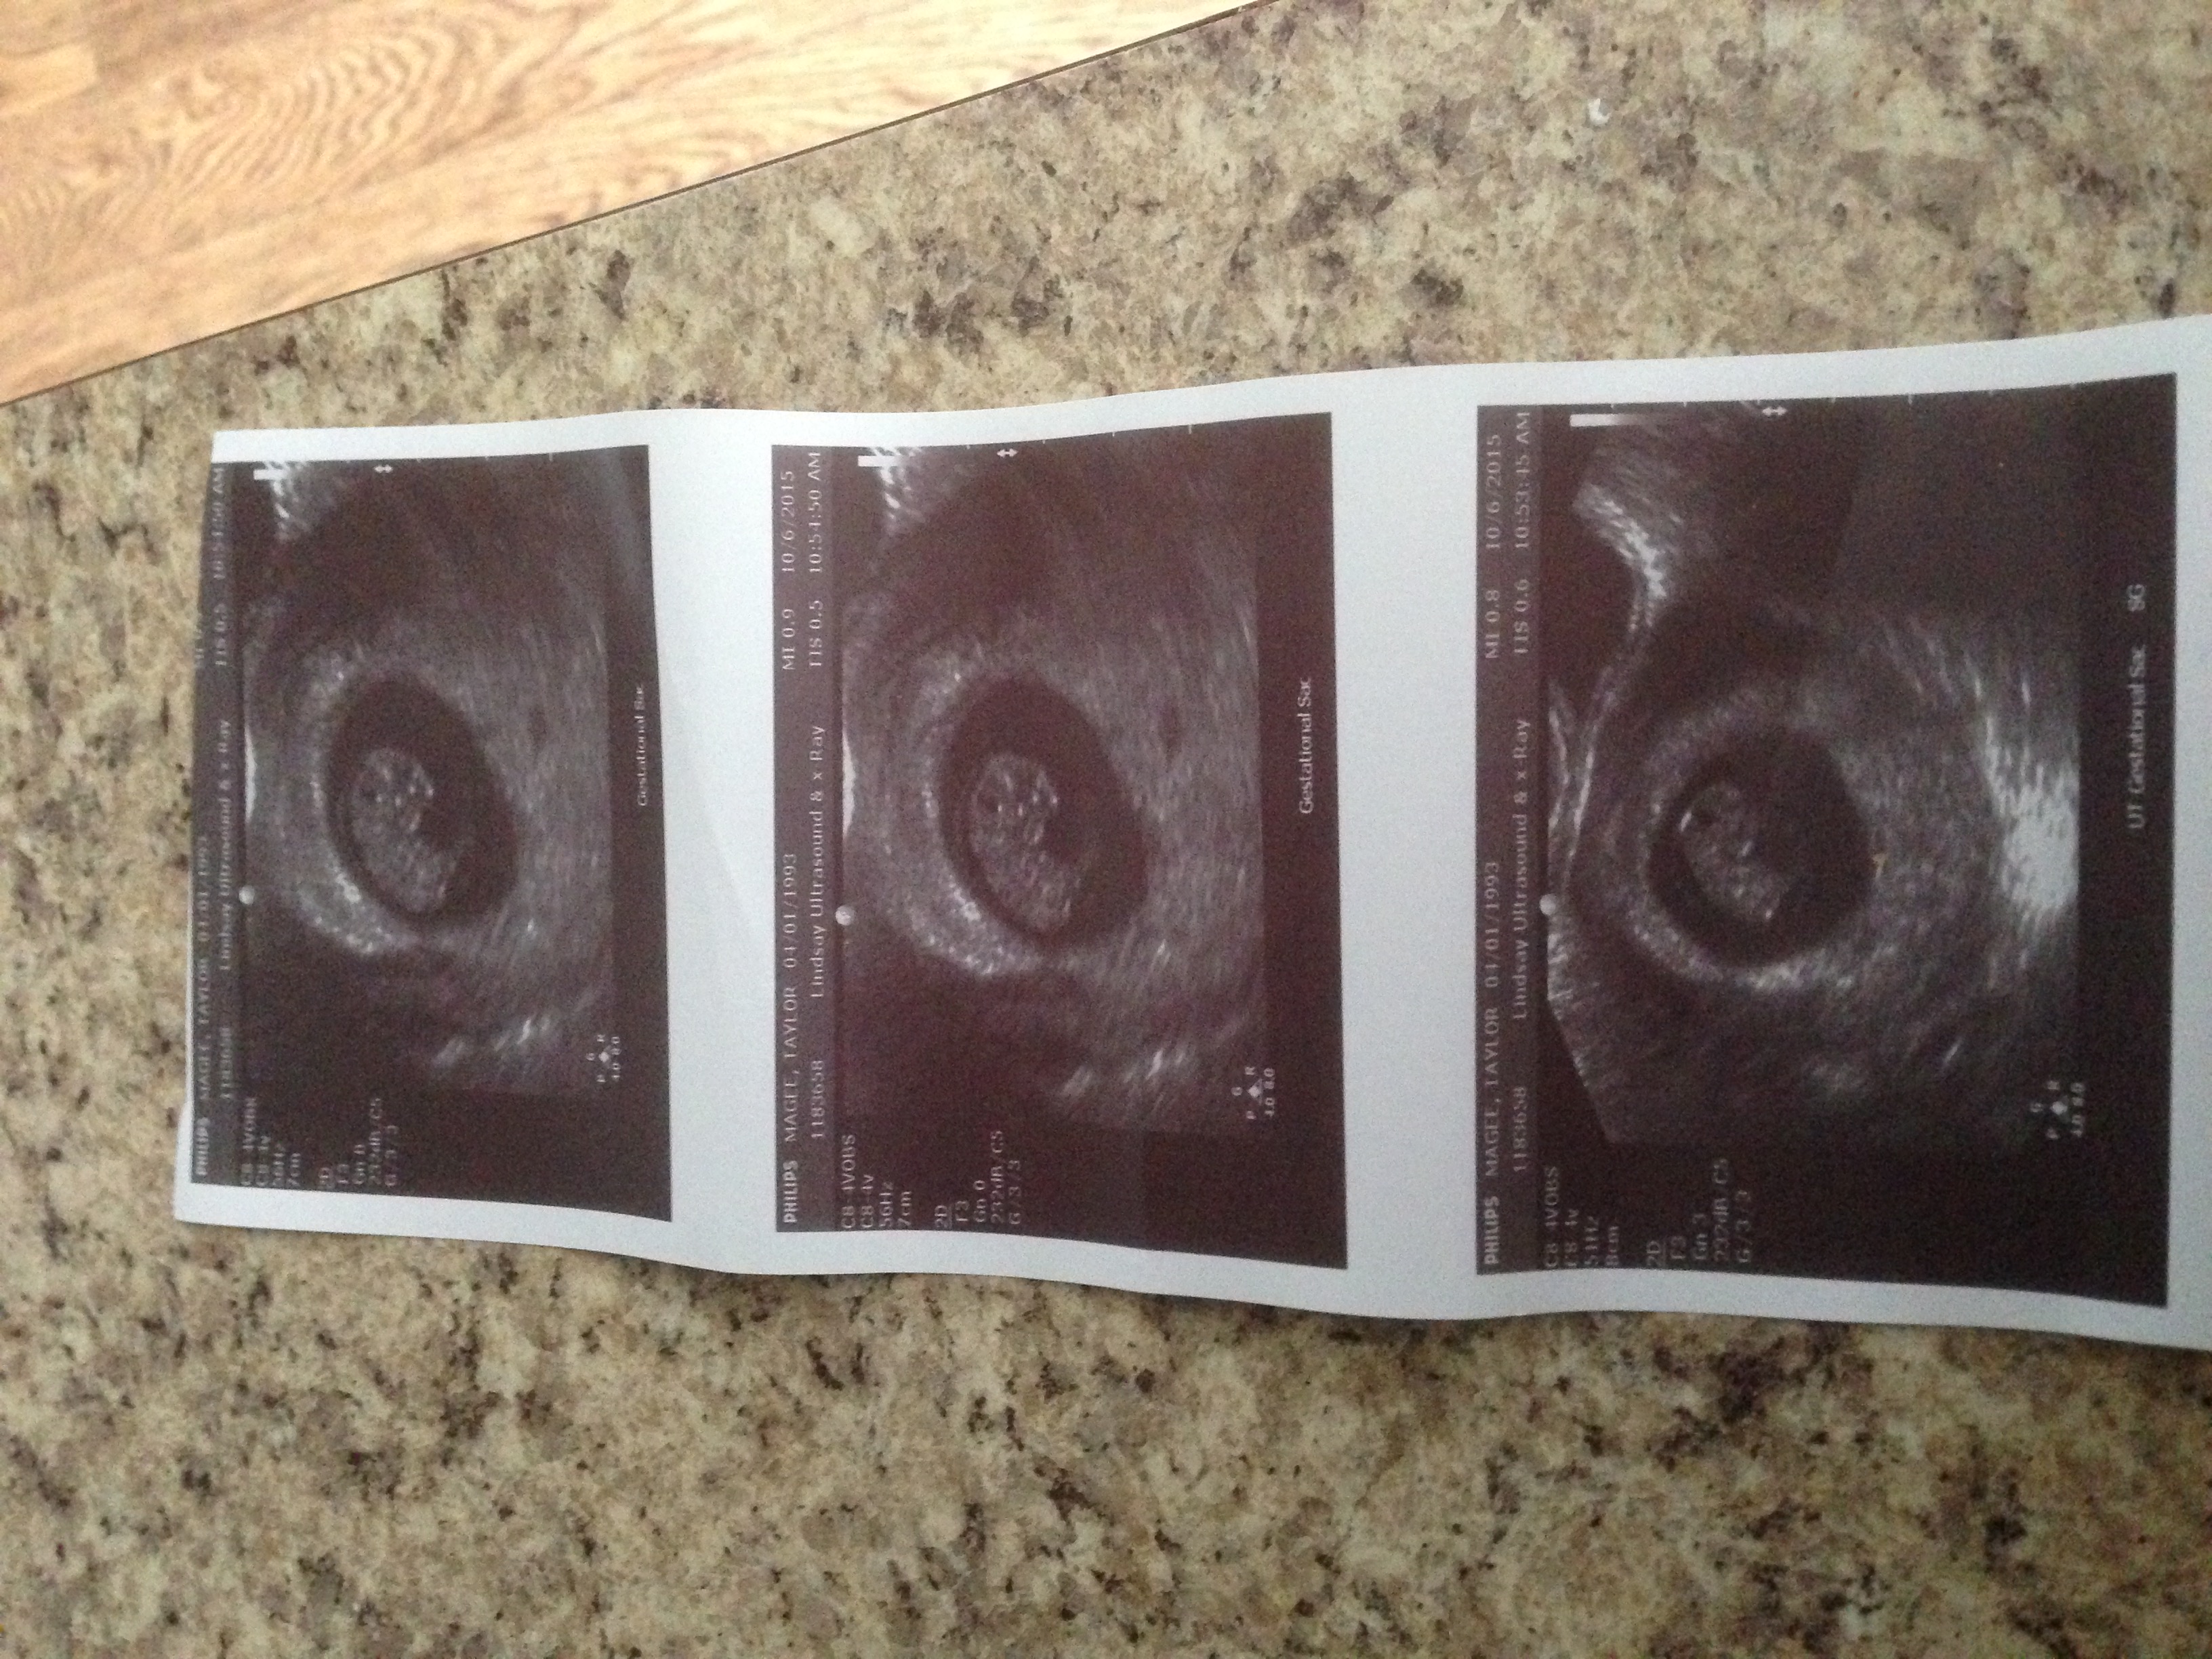

New discussion button is missing for me on my laptop. I had my first appt today expecting to be 8 weeks based on LMP. They did a transvaginal ultrasound because they were worried about a possible cyst and the sac was measuring at only 5w4d. You couldn't see anything in it yet. Based on when I think I ovulated, this would make sense... my cycles are usually long... but that didn't stop me from bursting into tears. Neither the tech or the doctor were worried and they want me to come back in 2 weeks for another ultrasound, but I'm freaking out. Is 5w4d just too early to see anything? Did anyone else have their EDD completely wrong when they went for an ultrasound?

If your cycles are unusually long, you shouldn't have based how far along you thought you'd be on your LMP. So, if you are only 5w4d, seeing the gestational sac sounds fine. I only saw the gestational sac at 5w2d, saw the yolk sac four days after that and saw the heartbeat at my 7w appointment. I know it's really hard (especially when so many other women see things a lot earlier), but try to remain calm and think positively.